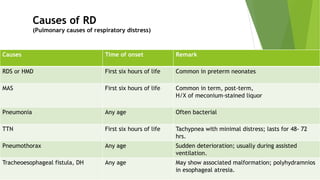

This document discusses respiratory distress and respiratory distress syndrome in neonates. It defines respiratory distress and describes the clinical signs. Various pulmonary and non-pulmonary causes are outlined. Respiratory distress syndrome, also known as hyaline membrane disease, is described in detail, including risk factors, pathophysiology, clinical presentation, investigations, complications, prevention, and treatment approaches like surfactant administration and nasal continuous positive airway pressure. The prognosis depends on gestational age and quality of care provided.